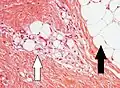

Lipoblastos (flecha blanca) y adipocitos (flecha negra), en un caso de lipoblastoma